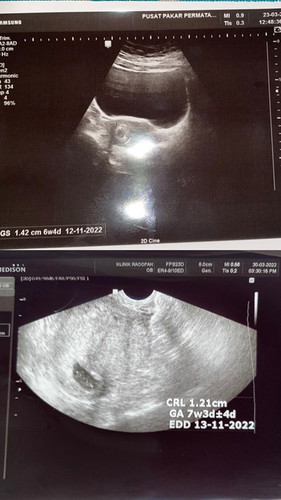

1:30am- sakit cramp teruk sangat. Terus call parent utk ke emergency. 2:00am- doctor scan perut and nak buat urine test. Masa saya cangkung nak dapatkan urine, terkeluar seketul darah sebesar bola tennis. Allah 😨 saya terus ambik darah tu dan tanya nurse. Nurse cakap tu blood clot. 3:00am- saya terus ke bhgn sakit puan utk check up. Sakit mcm period cramp tp teruk sangat and tak berhenti. Saya taktahu tu sakit contractions sbb tak pernah pregnant dan beranak. Saya diam dan tahankan saja sakit tu. Bila check, baby dah dekat pangkal rahim 😢 Ya Allah luluhnya hati masatu. Doctor terpaksa keluarkan baby. Saya sedih + sakit contractions + sakit kena robek bhgn bawah 😭 4:30am- Doctor sahkan complete miscarriage dan kena warded sehari utk pemantauan. Sempat tengok baby dalam bekas. Ada kaki tangan mata 🥺 sedihnya rasa. Lepas selesai scan and ambik darah, jalan kaki dari bilik pemeriksaan ke ward. Terbongkok bongkok dah badan sebab rasa sakit + ngilu. Jauh juga berjalan. Parent saya suruh balik rumah utk uruskan bersahur dgn family. 5:30am- sampai katil ward and nak berehat. First time dalam hidup masuk ward. Katil lain semua penuh dgn ibu ibu yg tunggu masa nak beranak. Comel comel perut. Saya sorang sahaja admitted sebab gugur. Semua sedih tengok saya tapi tak apa, at least saya ada pengalaman uruskan diri sendiri sorang sorang dkt hospital. Settle tukar baju, baring baring sambil tengok battery phone pulak tinggal 3%. Alahai dugaannya mcm drama. Video call dengan husband nak bagitahu dah miscarriage 😢 Husband saya dah lah jauh belayar. Line pun ada tak ada tengah laut hmm. Mengharapkan battery 3% tulaa kami video call sambil menangis kehilangan kandungan pertama kami. Semoga Allah gantikan lagi akan datang dengan rezeki baby 😢🤲🏻🤍 saya yakin ada hikmah. Terima kasih ya yang banyak follow kisah pregnancy pertama saya. Yang banyak tolong dan bagi nasihat dalam ni. Yang banyak guide dan bagi tips. Tak ada rezeki saya nak peluk kandungan saya. Sebenarnya, melalui apps ni banyak bantu ibu ibu yang muda, yang baru pregnant, yang mencari jalan penyelesaian and kata kata semangat. Korang banyak sangat sangat membantu. Saya pulak tak ada kawan yg sama umur 25 tahun dgn saya yg mengandung so tak dapat nak bertanya pendapat dgn rakan sebaya. Semua pun tak ada pengalaman. Terima kasih ya 🤍 Ikutkan due date baby keluar 14/11/2022 nanti, tarikh saya dan suami nikah 14/11/2021. Tak ada rezeki saya nak sambut kandungan pertama saya 🥲 tak apa lah, saya dan suami cuba untuk belajar redha. Salam sayang buatmu anakku yang ku namakan Muhammad Aryan Uwais. 🤍 #Myfirstbaby